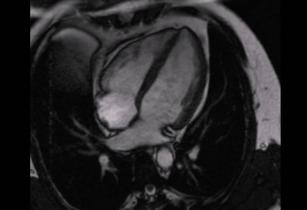

The fundamentals of left ventricular assessment in cardiac magnetic resonance imaging (CMR) 11th Sep 2017 - Andrew R. Houghton, MD Learn how to evaluate left ventricular size and function using cardiac MRI (CMR) from an imaging ...